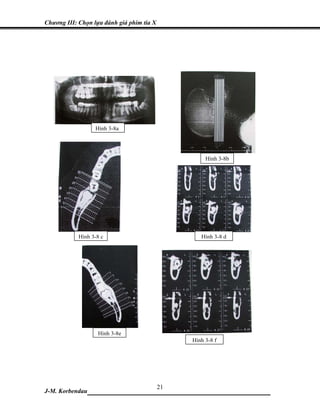

Hình 3-8a

Hình 3-8b

Hình 3-8 c                        Hình 3-8 d

Hình 3-8e

Hình 3-8 f

trình phẫu thuật (Lacan) (hình 3-8a).

mỏng từ 1 đến 1.5 mm, cách nhau từ 0.5 hay 1mm (hình 3-8b).

Đánh giá hình ảnh tia X này giúp làm rõ mức độ của các chân răng (hình 3-8c và 3-8e):

• Một đường cong dùng làm mốc theo điểm giữa của phần vỏ xương hàm. Các lát cắt

nên qua hay song song với những trục này. Các lát cắt này cũng nên qua kênh hàm

dưới theo chiều thẳng đứng nhằm khảo sát răng và ống hàm dưới.

•   Tái tạo các lát cắt xiên chéo theo hướng vuông góc với trục xương hàm dưới (hình

vòng cung).

•   Các lát cắt theo chiều xiên này phải được đánh số từ phải sang trái.

Sự tái tạo các cấu trúc cong trên PHIM TOÀN CẢNH

Chọn 3 đến 5 đường cong được tái tạo trên phim toàn cảnh, thường song song với cung

răng, cách nhau 2mm, và đánh số thứ tự từ lưỡi đến má: L1, L2, M3, B4, B5.

Có hai mức độ hình ảnh:

• Số thứ tự theo chiều đứng bên thể hiện vị trí và khoảng cách của các lát cắt

(thang chia độ theo mm).

• Số thứ tự đường cong theo chiều nằm ngang tương ứng với vị trí và khoảng

cách của cấu trúc cong được kiến tạo lại trên mặt phẳng (các mặt cắt vuông

góc với mặt răng). Chúng được đánh số từ phải qua trái.

Sự tái tạo cấu trúc theo chiều vuông góc với trục xương hàm dưới

Hình ảnh trên phim tương ứng với tiếp tuyến cung răng, không bị biến dạng trong phạm

vi má- lưỡi. Các cấu trúc lõm hay cong (như răng) cũng không biến dạng. Phim tái tạo cấu

trúc theo chiều vuông góc với trục xương hàm dưới cho thấy mối liên quan giữa các cấu

trúc giải phẫu với nhau. Hình ảnh của kỹ thuật chụp xiên góc để khảo sát R8 trong phim

quanh chóp (không thể thực hiện được trên phim toàn cảnh) thì có thể thu được trên phim

cắt lớp tái tạo này (hình 3-8d đến 3-8f).